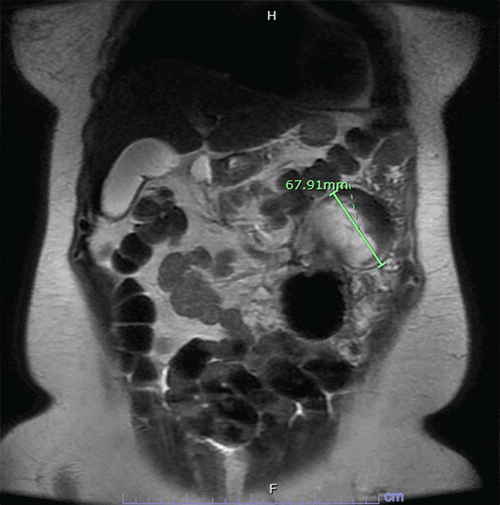

A 41-year-old woman presents with a triad of mild diffuse abdominal pain, nausea, and malaise. Abdominal CT scan revealed a 6 cm cystic-solid heterogenous complex mass in the left upper quadrant (Figure 1). Her past medical history is significant for morbid obesity, currently controlled hypertension, and prediabetes status following Roux-en-Y gastric bypass (RYGB) two years prior. Surgical history includes left salpingectomy for ectopic pregnancy in 2006 and total laparoscopic hysterectomy for cervical intraepithelial neoplasia grade 2 (CIN-2), dysfunctional uterine bleeding, and severe dysmenorrhea in 2011. Family history is notable for breast cancer in her sister and trisomy 4 in her eldest son. Physical exam revealed only mild left upper quadrant abdominal tenderness.

Figure 1. CT Scan of Well-defined Heterogeneous Mass in Left Upper Quadrant. Published with Permission

Horizontal view (★tumor)

B) coronal view